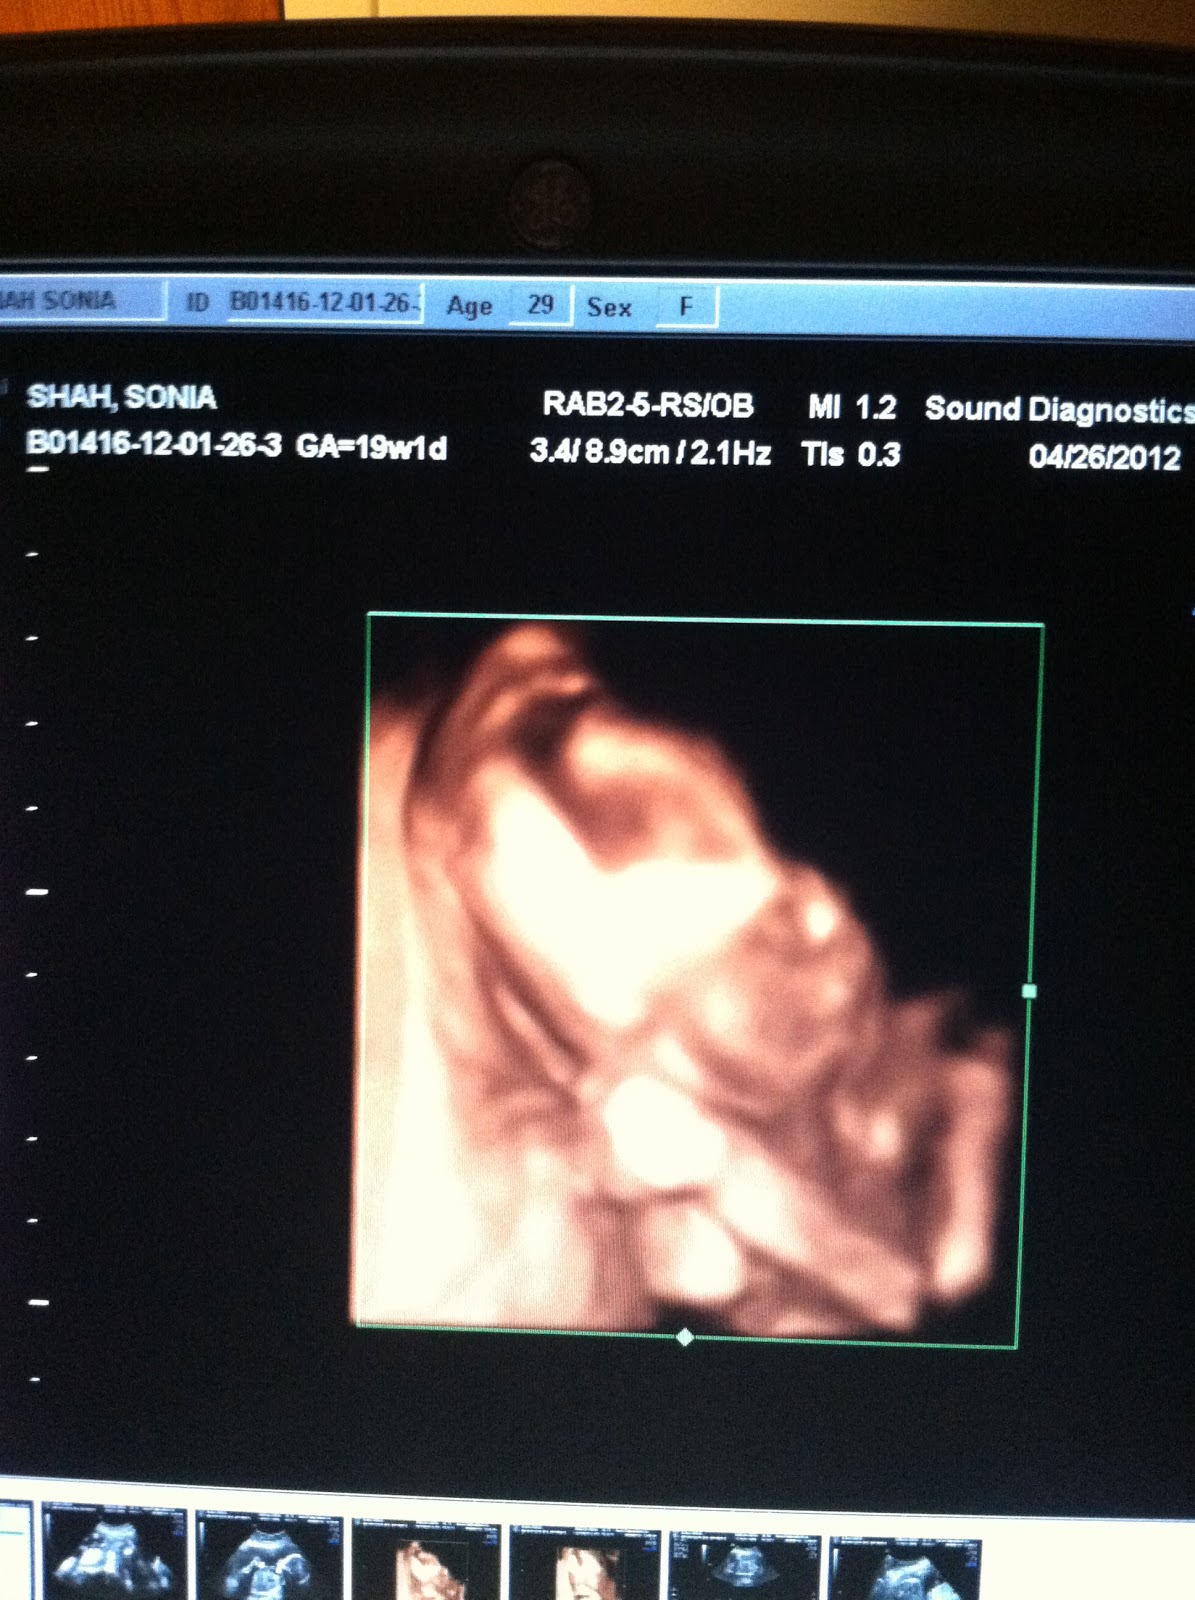

Meet Carina's sibling! Boy or Girl? We'll find out in September :)